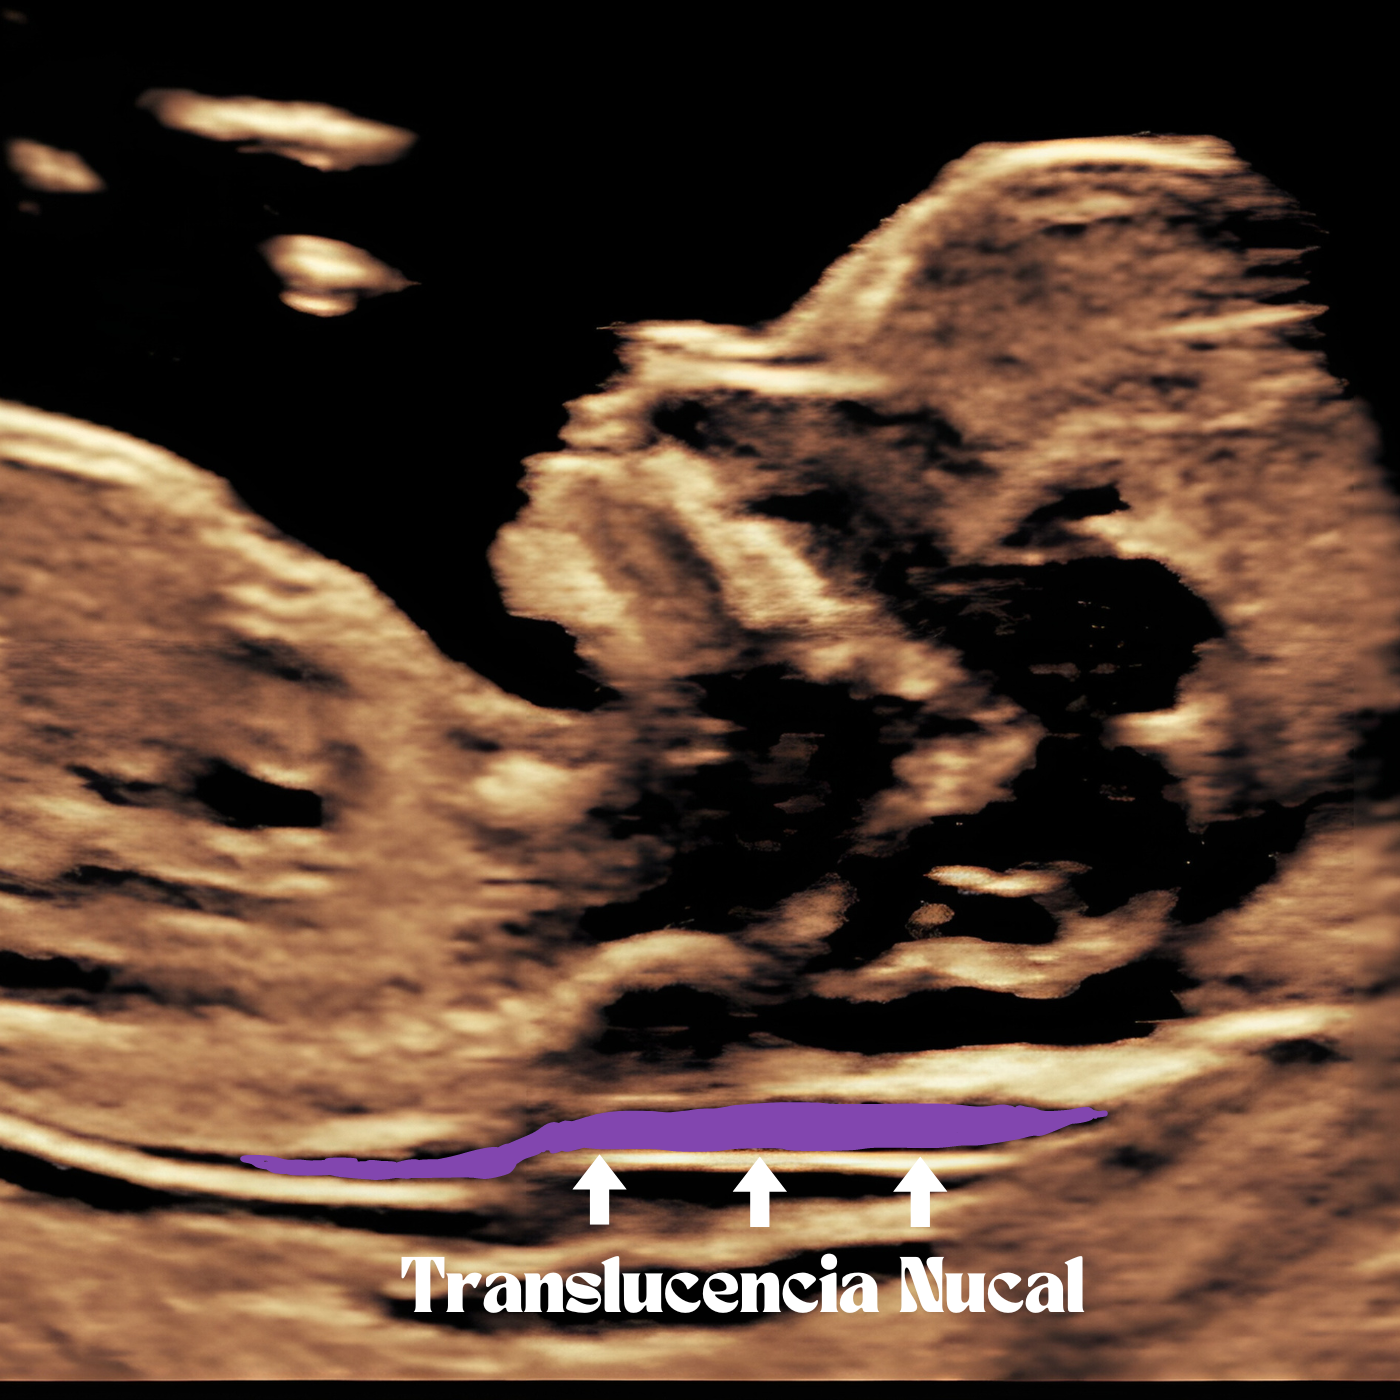

La Translucencia Nucal

La translucencia nucal es un marcador importante que se utiliza en el cribado de trisomía 21, 18 y 13. Es la representación ecográfica de la colección de líquido bajo la piel en la nuca del feto en el primer trimestre de embarazo. El grosor de la translucencia nucal en fetos genéticamente sanos aumenta con la Longitud céfalo nalga. En un 75-80% de los fetos con trisomía 21 el grosor de la translucencia nucal está aumentado.

Es importante recordar que el aumento del grosor de la translucencia nucal no determina definitivamente si el feto tiene una anomalía cromosómica, sino que ayuda a identificar aquellos casos que podrían beneficiarse de una evaluación adicional.

Los resultados de la detección de la translucencia nucal se presentan generalmente como un riesgo relativo, por ejemplo, 1 en 1000, lo que indica un bajo riesgo o probabilidad de que el feto tenga una anomalía cromosómica.